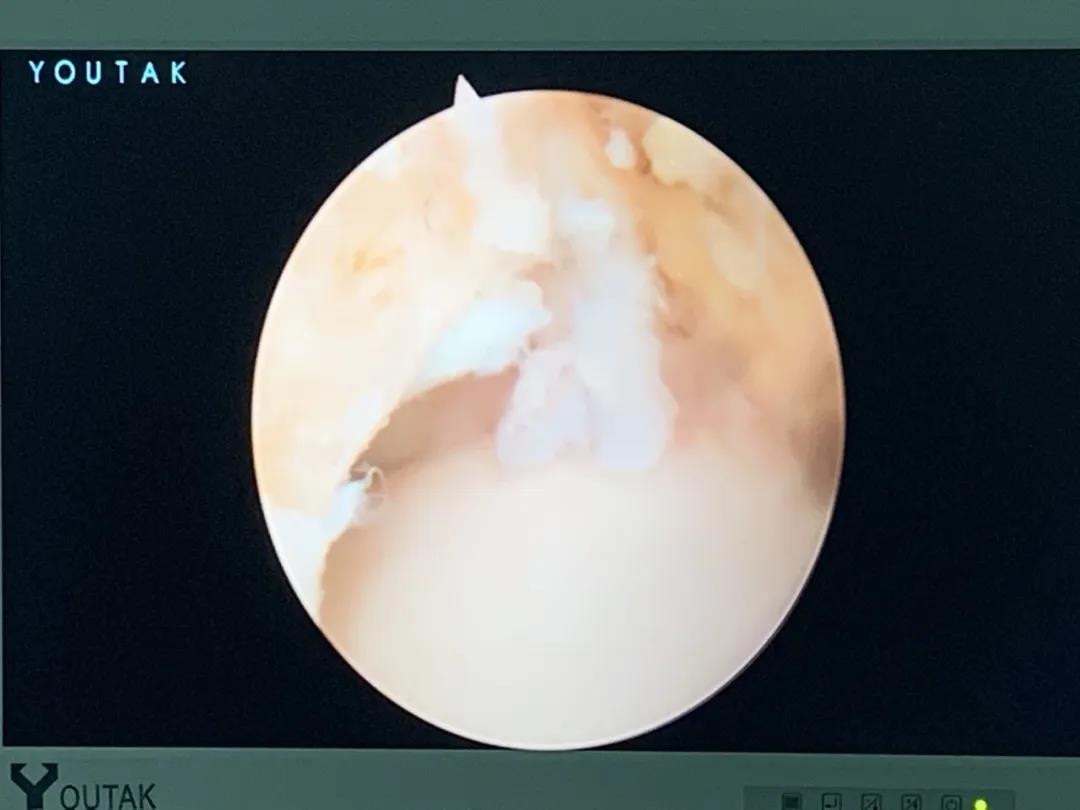

膝關節(jié)鏡

膝關節(jié)半月板損傷和前后交叉韌帶損傷是運動損傷常見疾病,半月板損傷后不能自行愈合,盡早手術可以避免繼發(fā)關節(jié)軟骨的損傷,骨二科采用關節(jié)鏡下半月板縫合手術,能少切除就少切除,能縫合盡量縫合,最大努力保留患者半月板,更好的恢復膝關節(jié)的功能。膝關節(jié)前后交叉韌帶損傷一般采用單束重建,只能恢復原來韌帶的80%的強度,骨二科采用雙束重建,能夠比原來的韌帶更粗更強,為后期的功能鍛煉及恢復提供良好的基礎。

關節(jié)鏡下半月板縫合手術

關節(jié)鏡下雙束重建